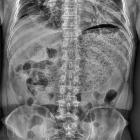

Plain radiograph

- marked enlargement of the gastric shadow filled with air

CT

marked gastric dilatation in the absence of mechanical obstruction or gastric masses